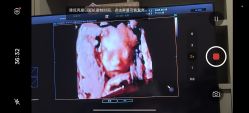

• 郑州万安妇产医院

• -郑州万安妇产医院

Melony. 上传于 25-08-30 | 报错